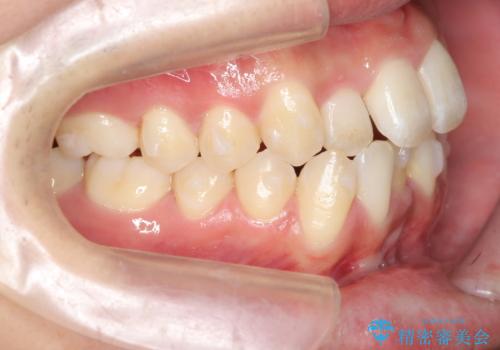

- 前歯のガタガタを主訴に来院。

下の前歯が3本になり奇数になることで、上下の真ん中は一致しませんが、そこまで目立たないと思います。

残りは全て天然歯になり、人工物の心配をしなくて済むようになりました。

治療も順調に進み、リファインメントも1回のみで済んでいます。

ブラックトライアングルも少なめで、短期間でしっかり並びました。

上の前歯のガタガタも、わずかに歯を削って並べていますので、出っ歯になったりしないようにしています。